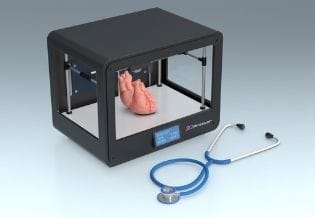

2026-06-03 10:18:103D Printing and Applications

ISSN :2831-8846

Journal 3D Printing and Applications covers the latest advances in 3D printing and applications that support COVID-19 relief initiatives, 3D Printing ...

2026-06-03 10:18:11Organ Transplantation

ISSN :2576-9359

Organ Transplantation is the journal for medical professionals exploring the latest research in liver biopsy, Organ Transplantation Medicine, xenotran...